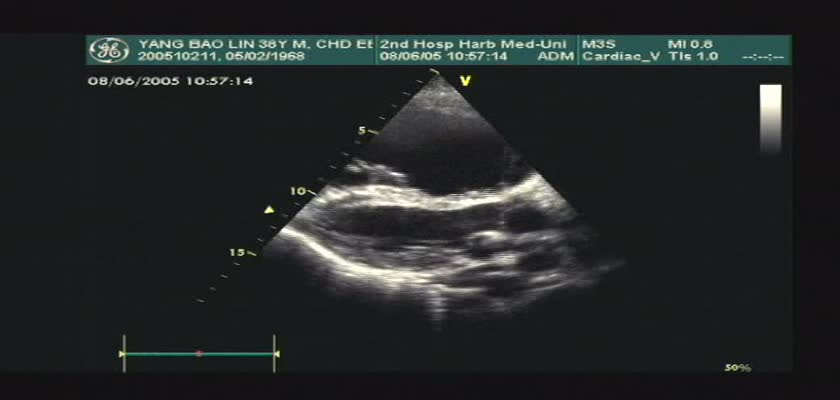

先天性心脏病超声诊断-先天性心脏病超声诊断视频20